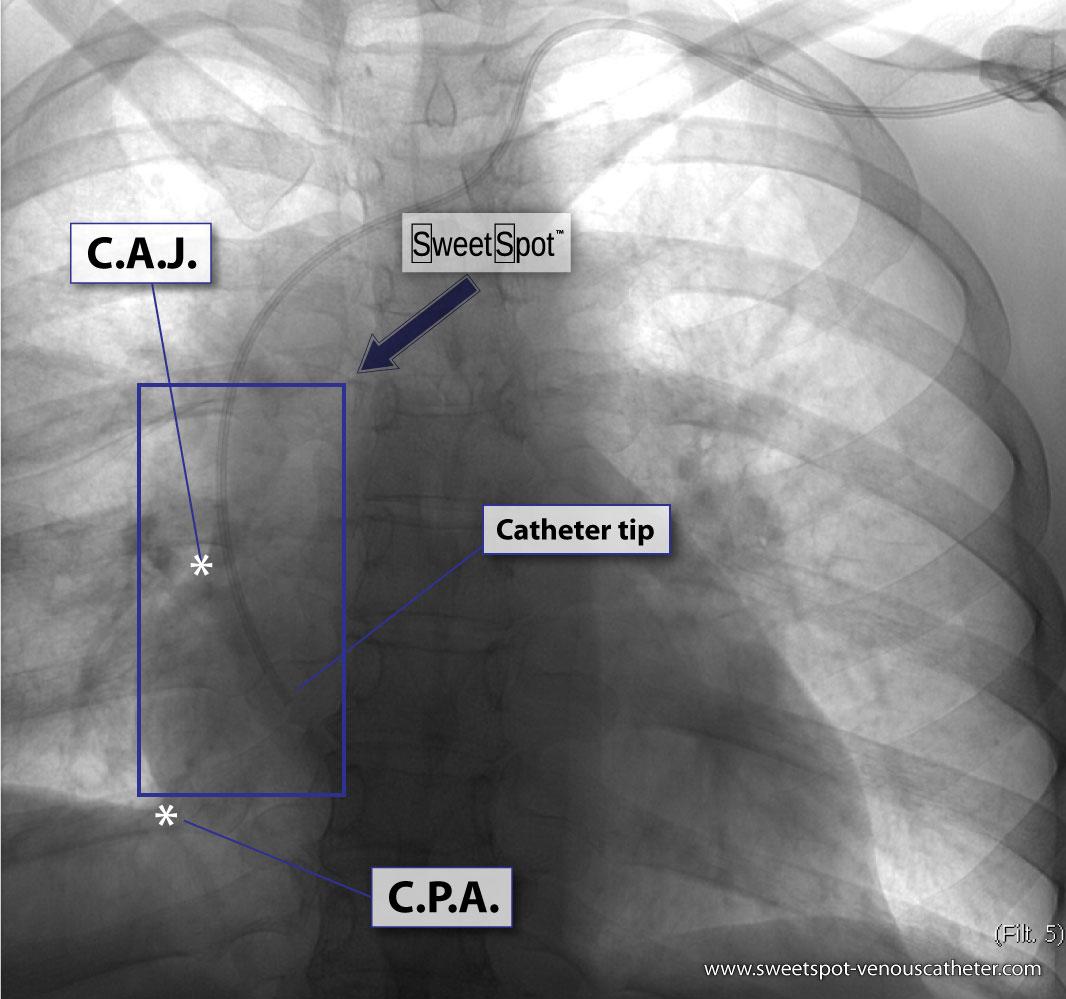

Enhanced coronal CT reconstruction |

Figure - 05